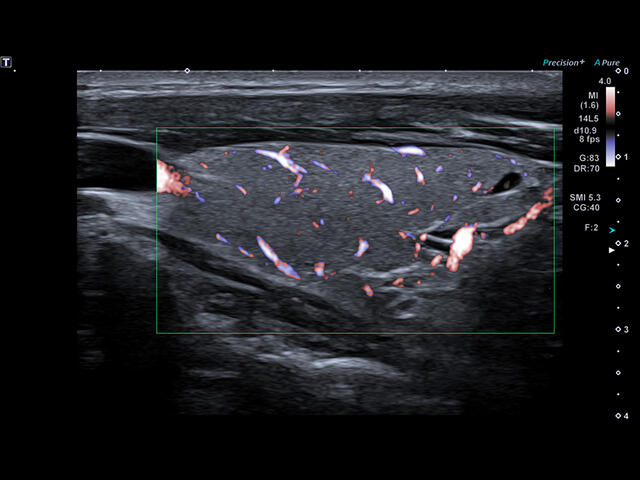

- SMI. Опция, упрощающая визуализацию микроциркуляторного русла. С ее помощью обследуются сосуды с низкой интенсивностью кровотока, изучаются наиболее тонкие структуры. SMI упрощает диагностику новообразований, минимизирует вероятность ошибки.

- Режим визуализации микро кровотока: SMI

Уровень сосудистой визуализации SMI в сочетании с высокой частотой кадров повышает диагностическую достоверность при оценке поражений, кист и опухолей.

SMI с цветовой кодировкой позволяет одновременно отображать информацию о потоках и оттенках серого с высокой временной и пространственной информацией.